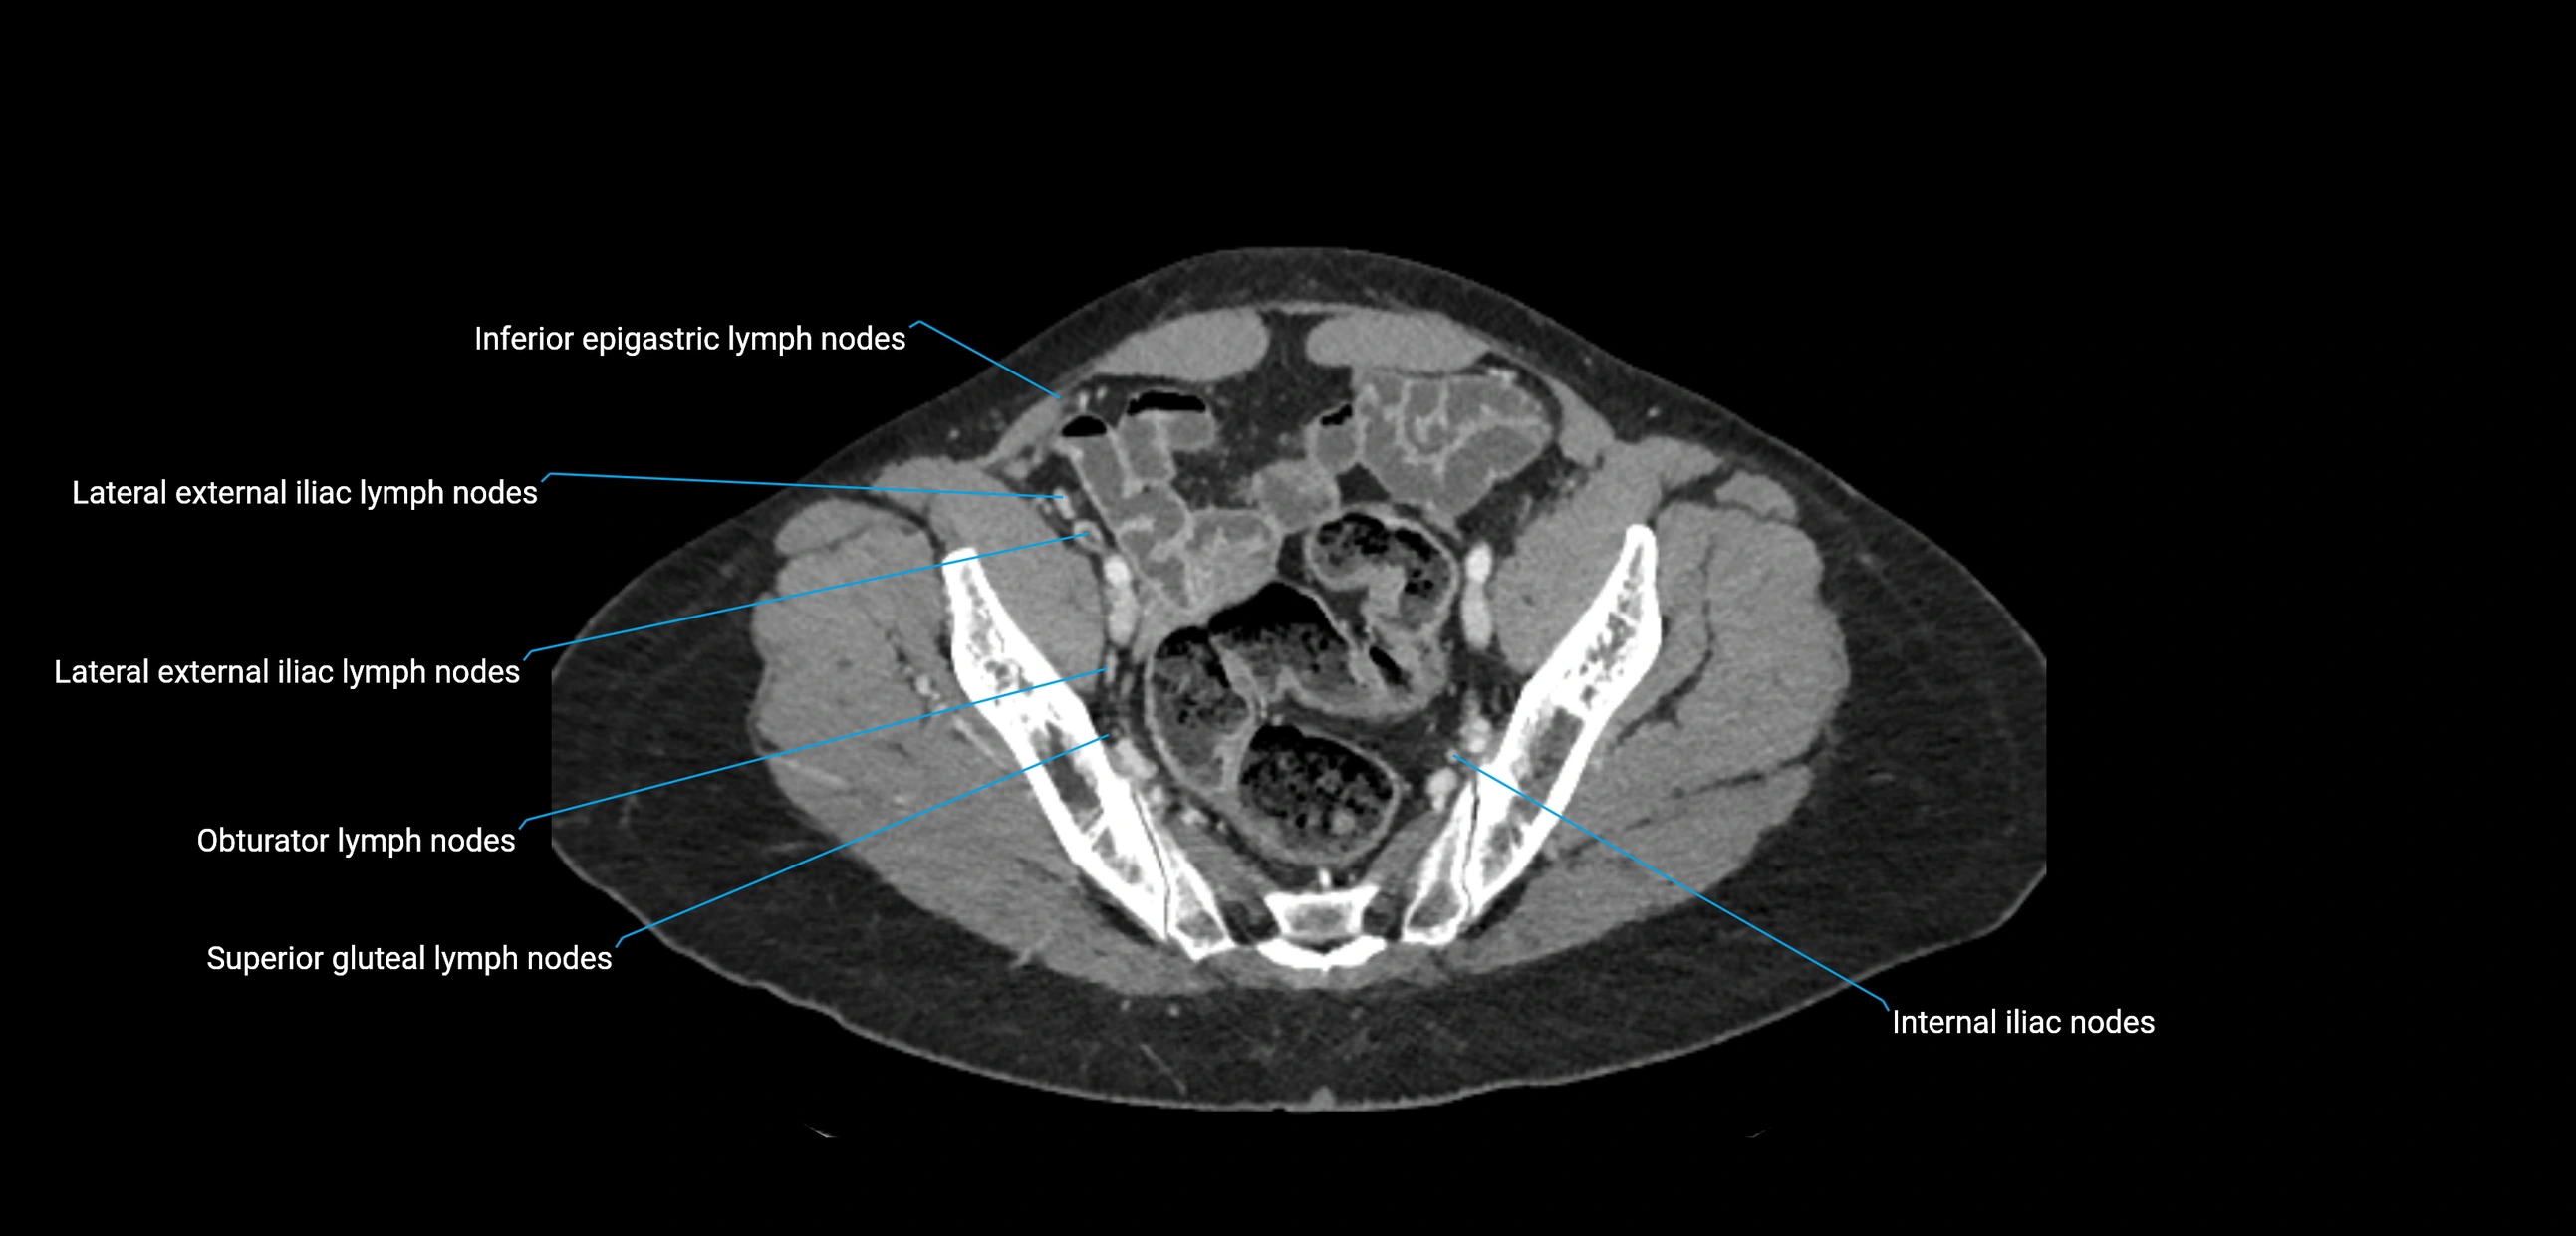

CT image

image